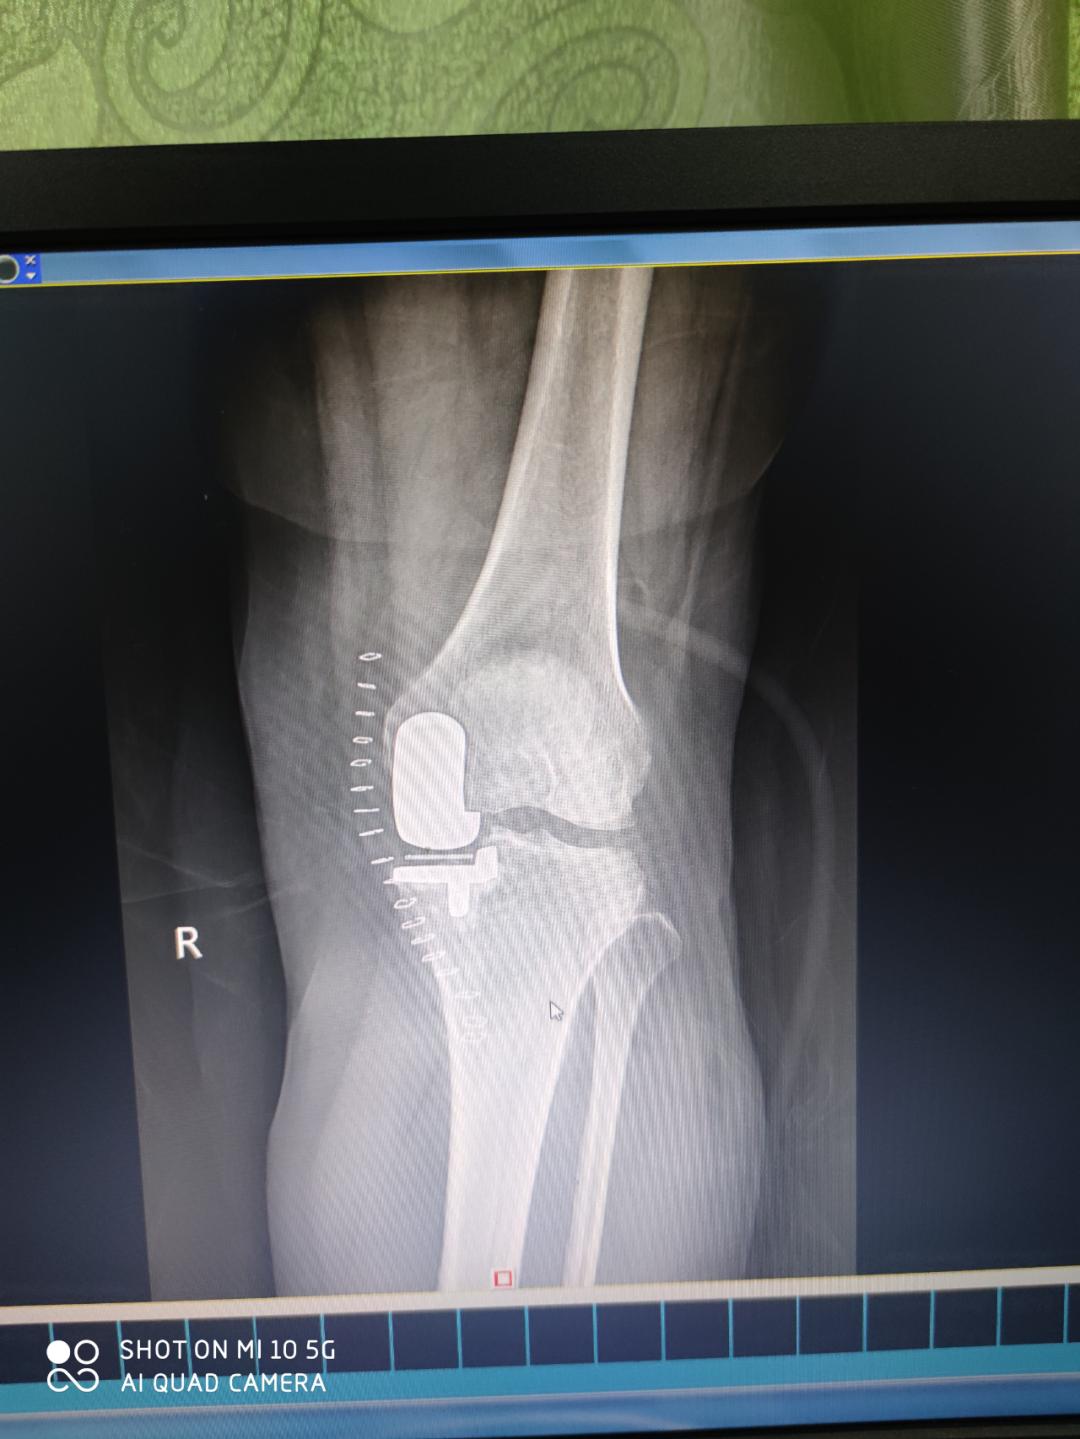

患者张女士,58岁,因左膝关节疼痛1年余,加重4个月后到百色市人民医院关节外科住院。患者告知,其左膝疼痛严重,白天及夜间疼痛明显,活动时加重,严重影响生活及日常工作。她曾在外院多次治疗,但是无明显效果,至今左下肢无法负重行走,经熟人介绍后,到百色市人民医院门诊就诊,诊断为“左股骨远端自发性骨坏死”而收住医院关节外科。

术前

患者入院后,科室专家们为患者进行病情讨论,制定治疗方案,最终,一致认为该患者左股骨远端自发性骨坏死诊断明确,有明确手术的指征,结合患者目前的年龄、工作情况及其病情需要,可选择行左膝关节内侧单髁置换术(UKA)进行治疗,手术由农家隆、杨稀仁、陈俊、蒙华伦、陆吉利等专家共同完成。治疗效果非常显著,术后第二天患者就可以扶拐下床。

术后